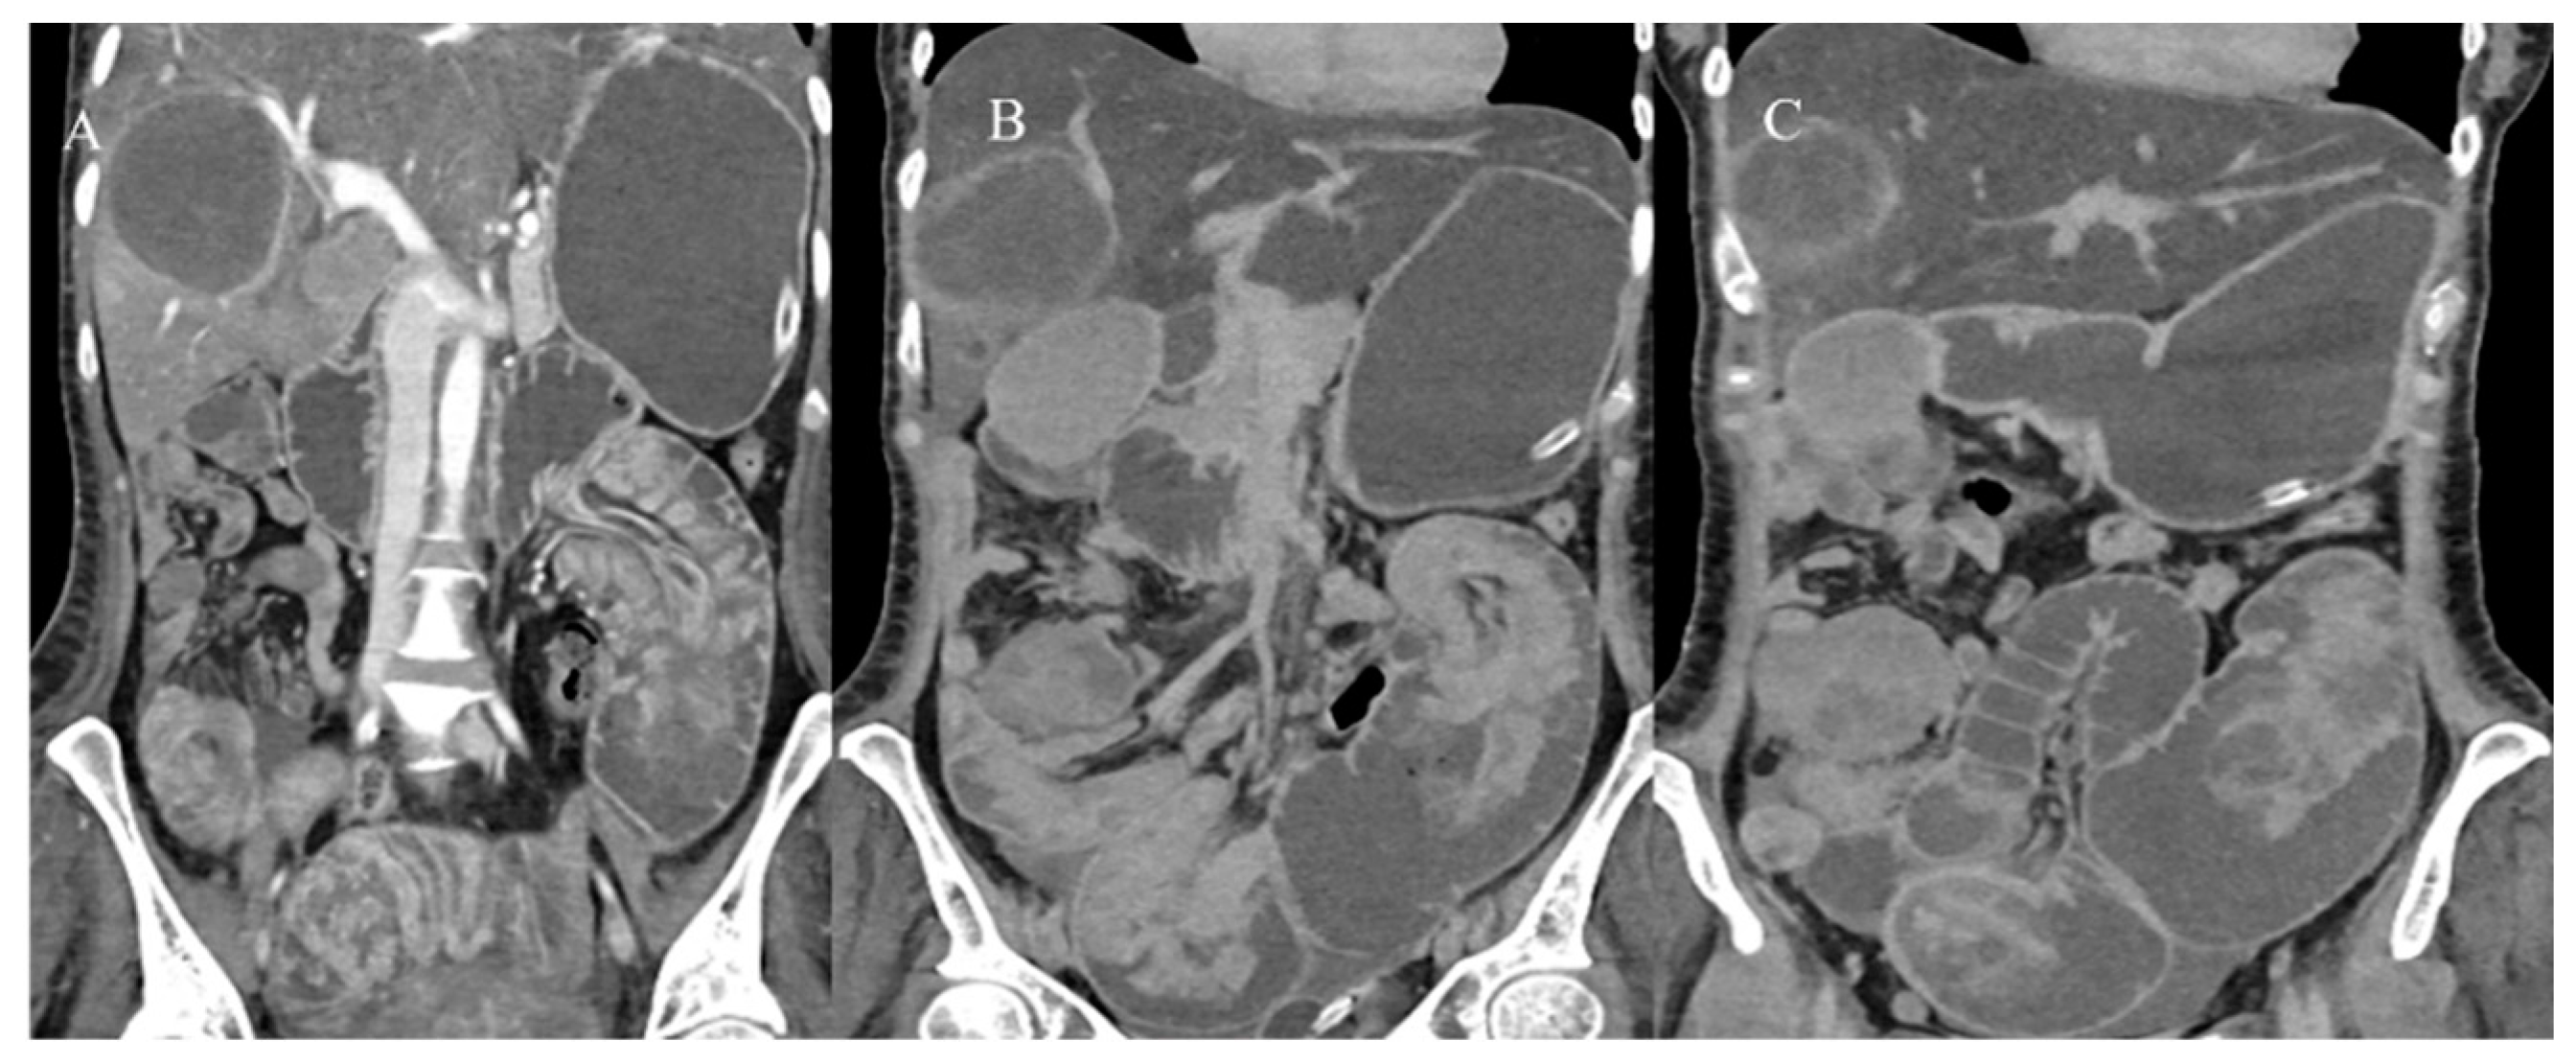

- Tran, C.G.; Sherman, S.K.; Howe, J.R. Small bowel neuroendocrine tumors. Curr. Probl. Surg. 2020, 57, 100823. [Google Scholar] [CrossRef] [PubMed]

- Ganeshan, D.; Bhosale, P.; Yang, T.; Kundra, V. Imaging features of carcinoid tumors of the gastrointestinal tract. AJR Am. J. Roentgenol. 2013, 201, 773–786. [Google Scholar] [CrossRef]

- Gupta, A.; Lubner, M.G.; Menias, C.O.; Mellnick, V.M.; Elsayes, K.M.; Pickhardt, P.J. Multimodality imaging of ileal neuroendocrine (carcinoid) tumor. AJR Am. J. Roentgenol. 2019, 213, 45–53. [Google Scholar] [CrossRef]

- Gangi, A.; Siegel, E.; Barmparas, G.; Lo, S.; Jamil, L.H.; Hendifar, A.; Nissen, N.N.; Wolin, E.M.; Amersi, F. Multifocality in small bowel neuroendocrine tumors. J. Gastrointest. Surg. 2018, 22, 303–309. [Google Scholar] [CrossRef]